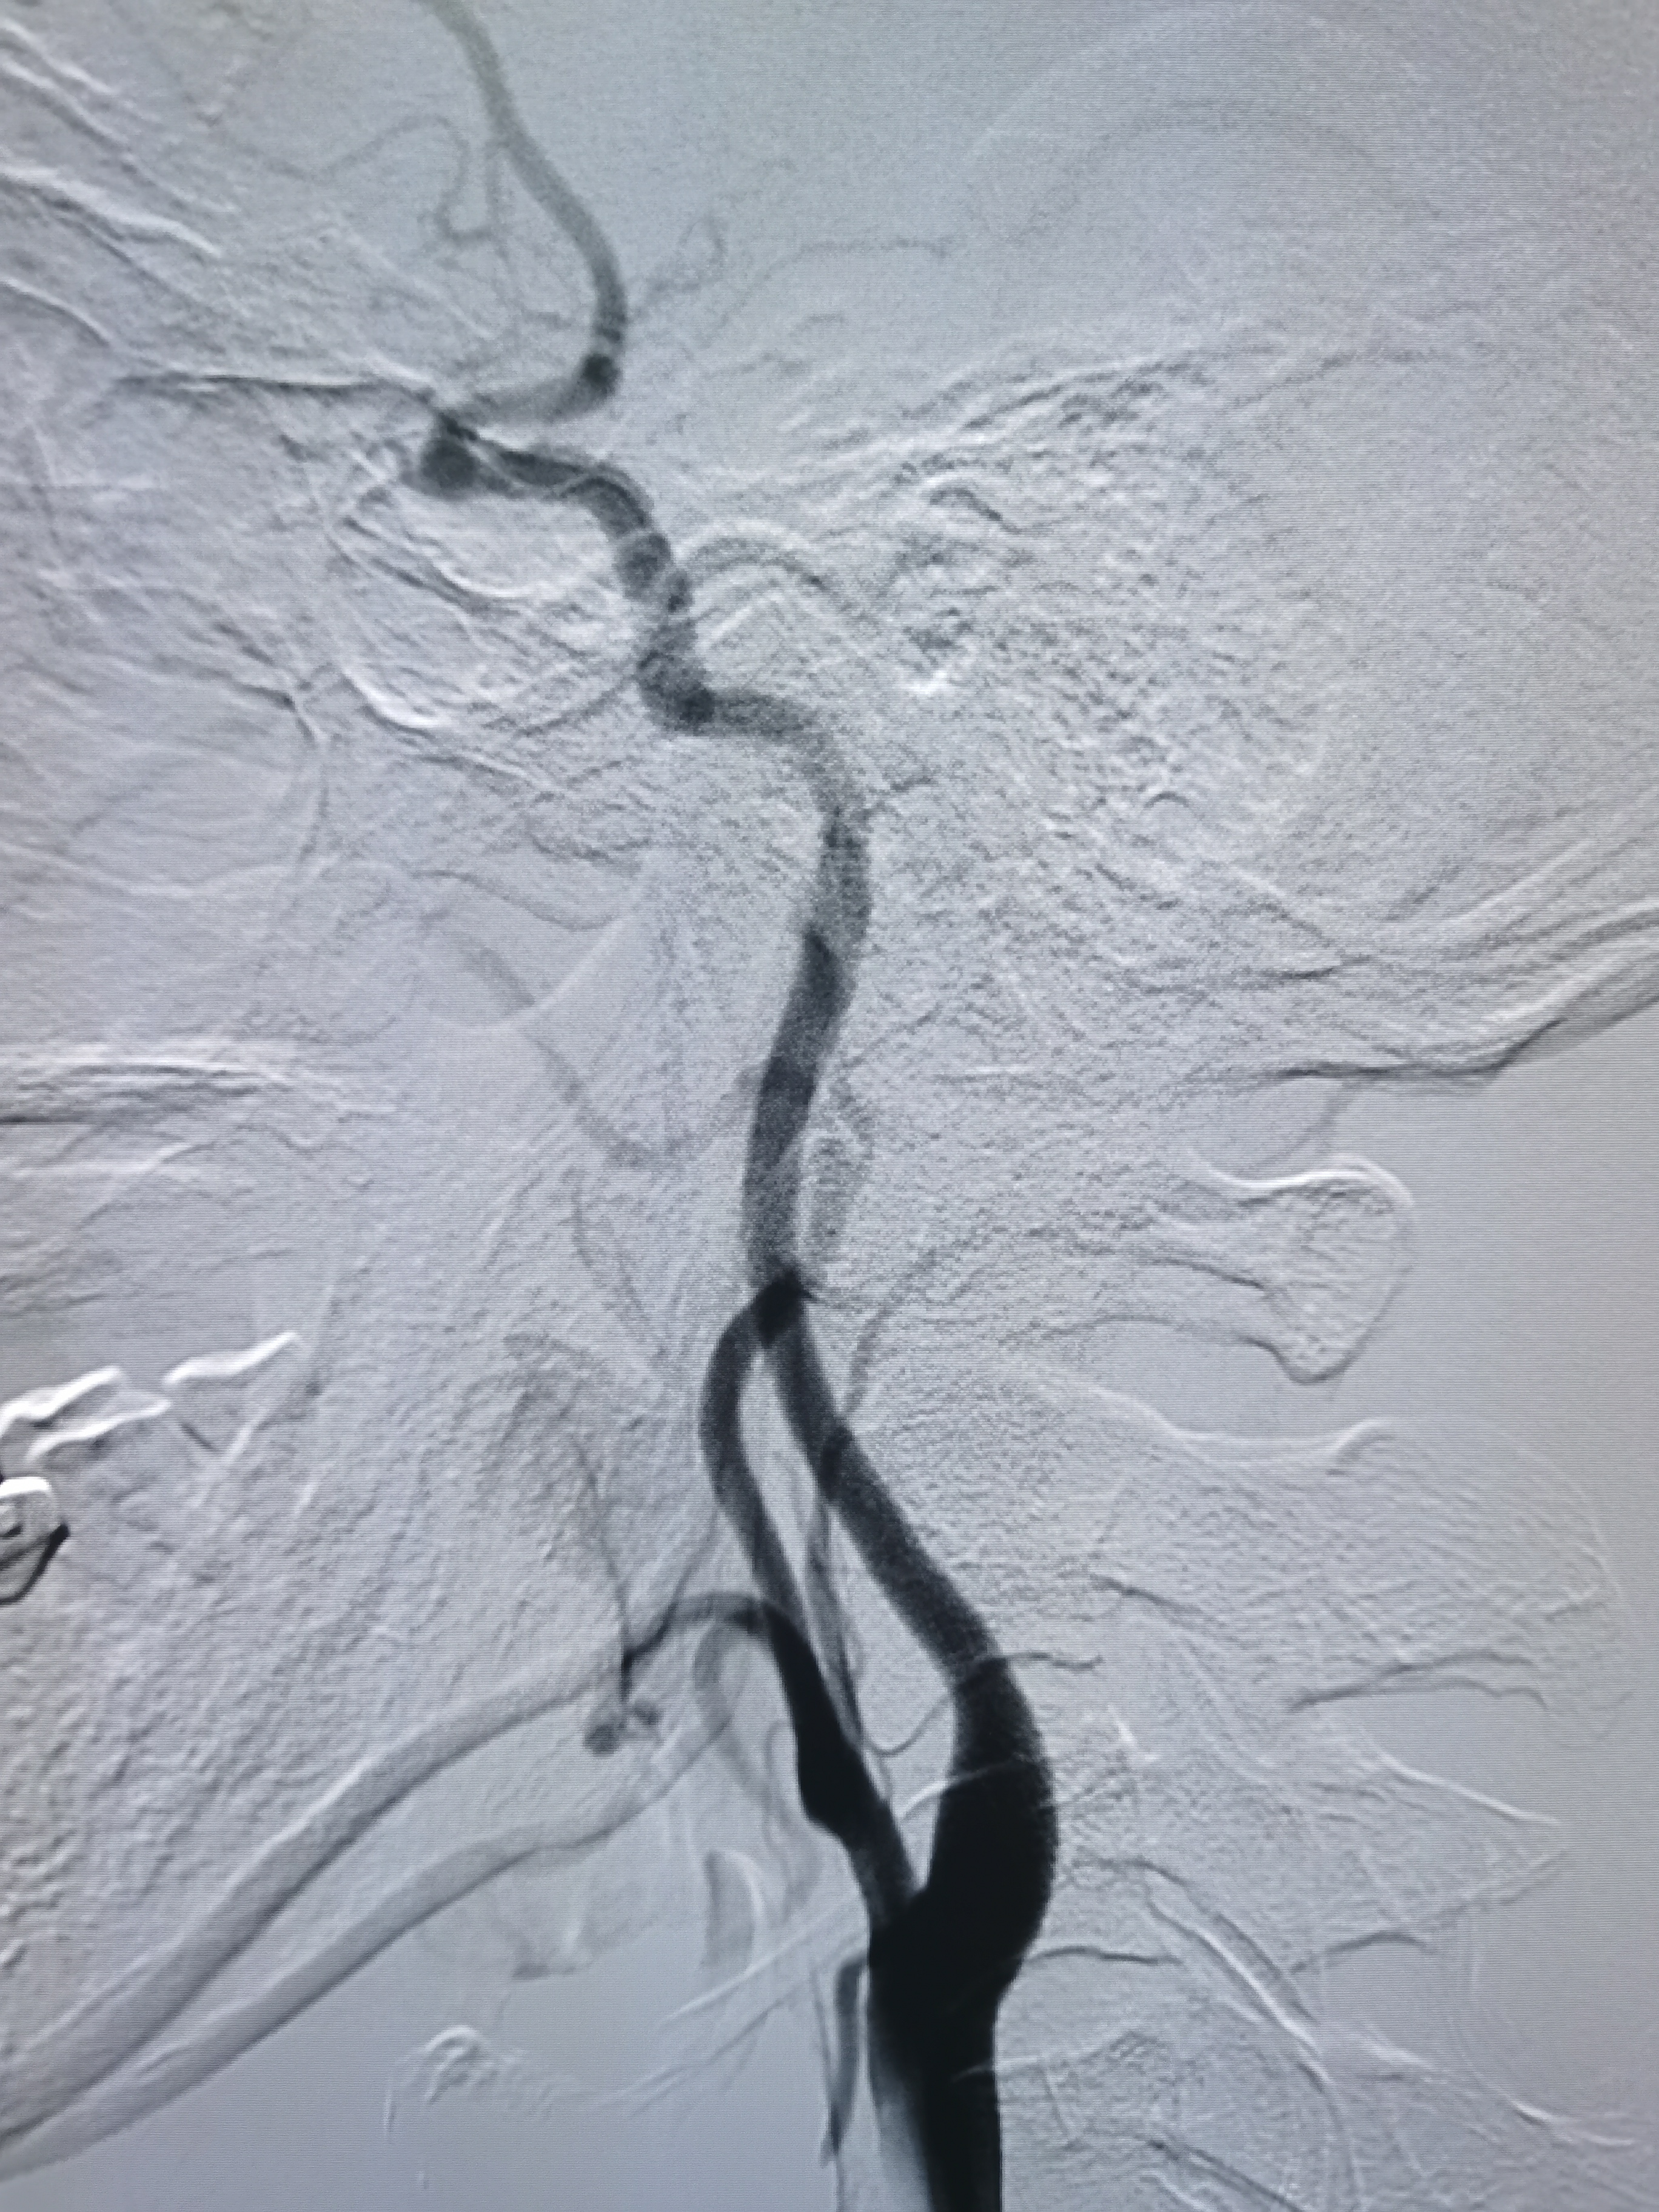

全麻后,将8F导引导管及中间导管顺利到位,建立路径,在路径图下微导丝携微导管顺利通过病变。

微导管确认位于真腔,交换入Transend300导丝。

2.0/15球囊扩张闭塞处。

扩张后造影见近端显影,远端血管仍闭塞。

将球囊前送,再次加压扩张。

扩张后造影见血管再通,血流通畅。